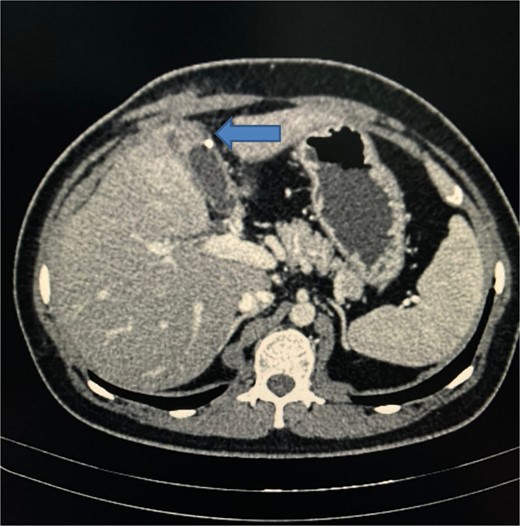

A CT scan of the abdomen revealed a walled-off fluid collection ~5.1 × 1.9 × 1.6 cm in the gallbladder fossa, penetrating segment 4a of the liver, with a small calcific density attached to the wall of this fluid collection. A soft tissue density tract-like lesion extended from the anterior aspect of the collection toward the subcutaneous plane of the right upper abdominal wall, suggesting a sinus tract (Fig. 3).

CT scan of abdomen showing a walled-off fluid collection with a small calcific density and a soft tissue density tract-like lesion extended from the anterior aspect of the collection towards the subcutaneous plane of the right upper abdominal wall, suggesting a sinus tract.